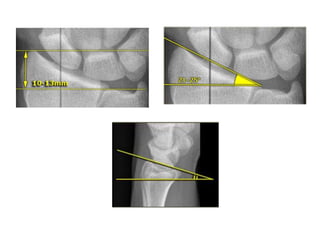

Parameters

https://www.orthobullets.com/trauma/1027/distal-radius-fractures